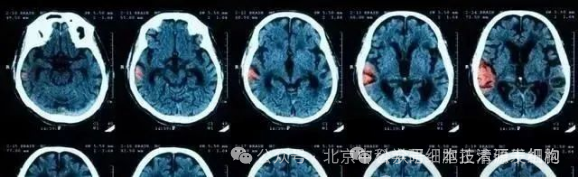

脑出血是神经内外科最常见的难治性疾病之一。

同为卒中,虽然相比脑梗死,脑出血只占20%~30%,但其死亡率最高可达68%。通常脑出血发病来势汹汹,约4/5的死亡发生在4天之内。

与人们的忌惮之心不相匹配的是,大多数人对脑出血一知半解,导致不能及时发现征兆并开展治疗。